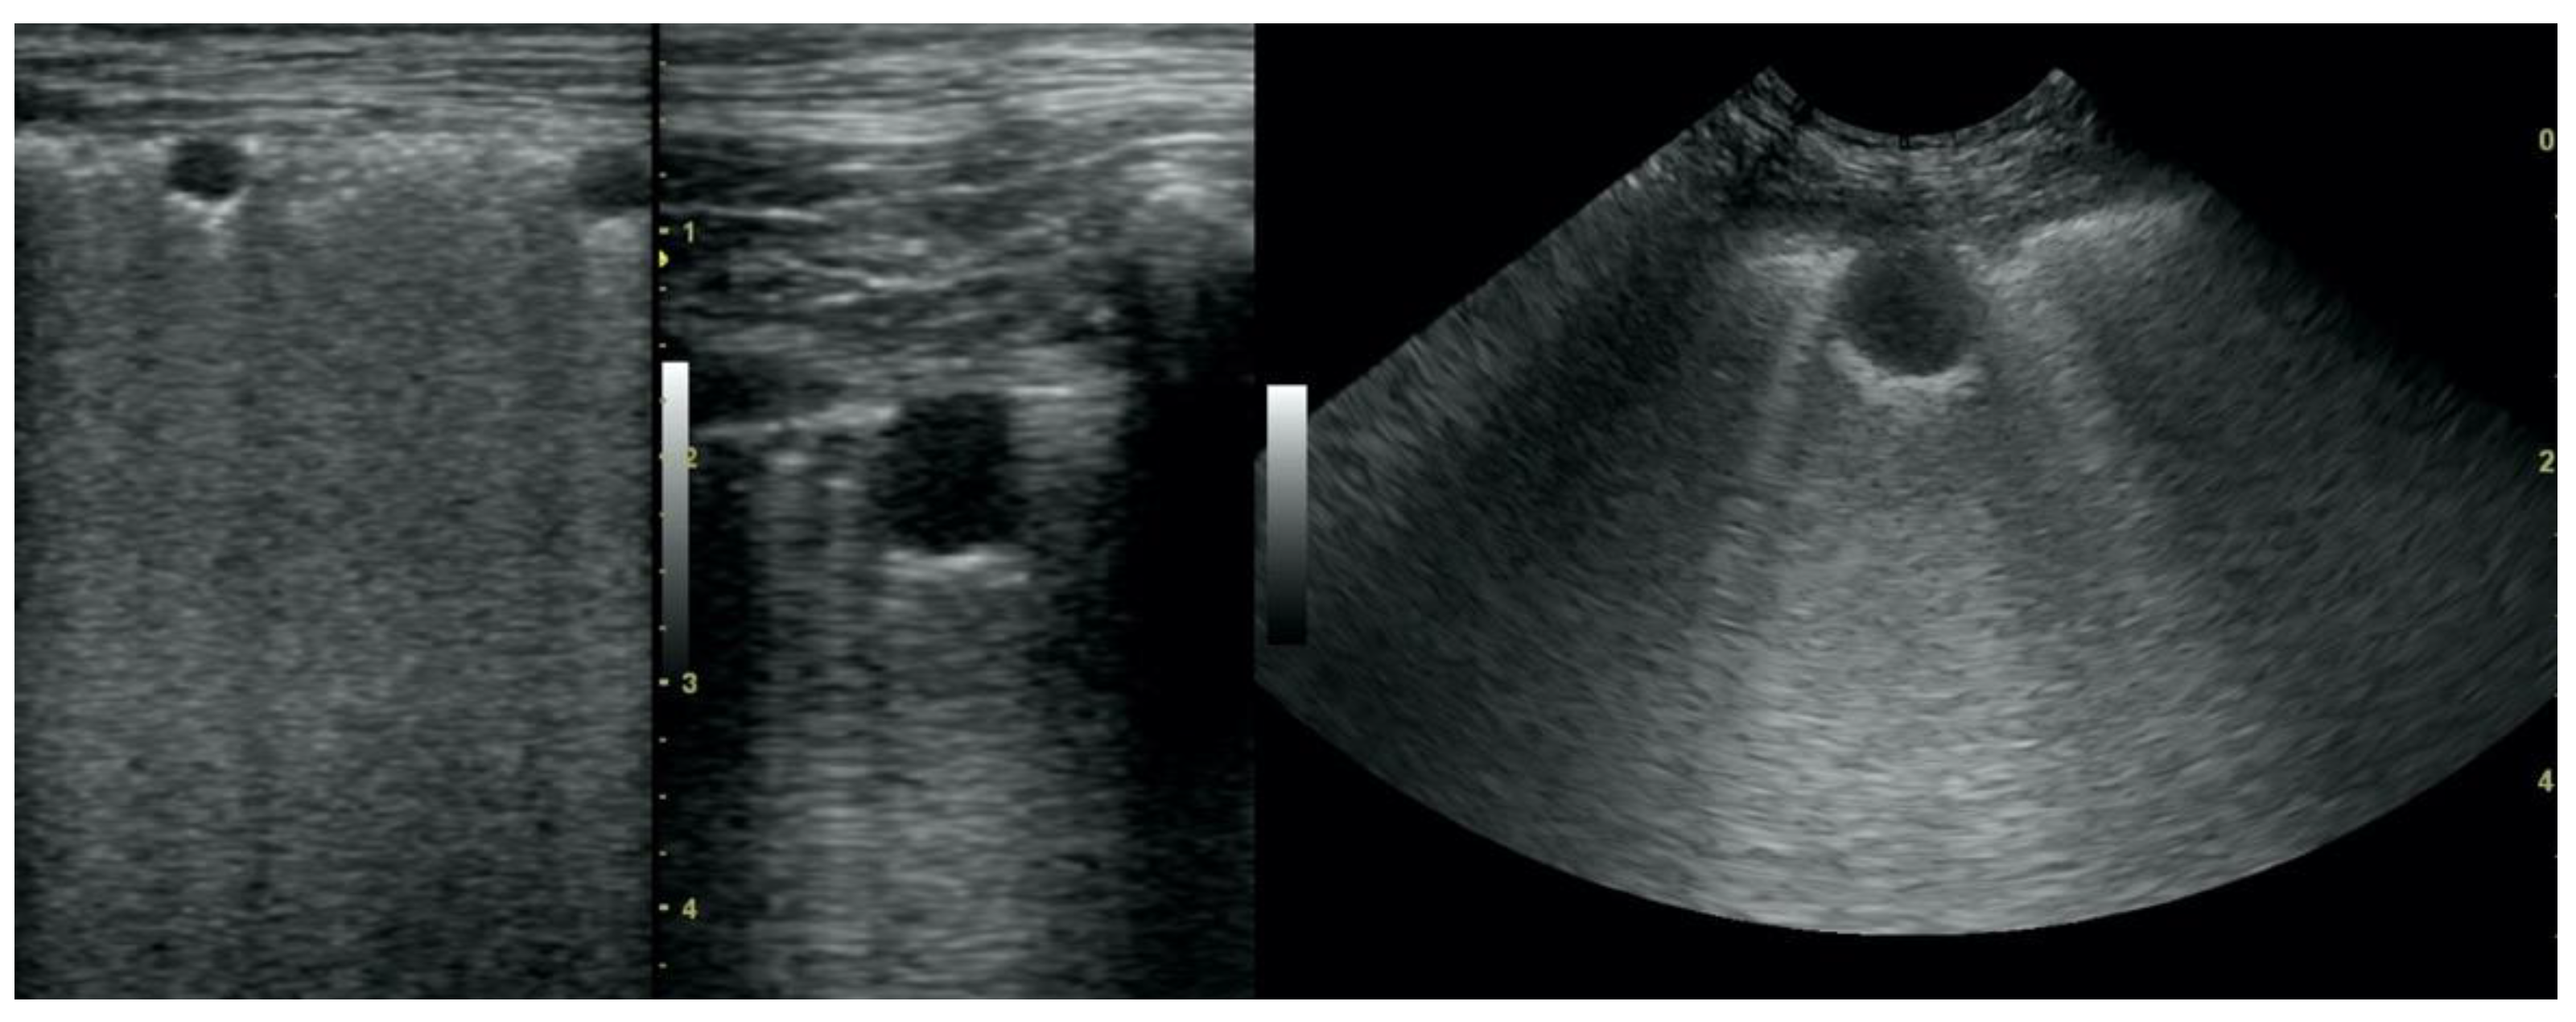

• Pulmonary nodules (≤3 cm in diameter), visualized as an anechoic or hypoechogenic area adjacent to the pleural line of round or oval shape, often with visible B-lines extending from its lower edge (Figure 8), and pulmonary masses (>3 cm in diameter), usually appearing as hypoechogenic masses with a clear-cut deep margin (Figure 9). Pulmonary nodules and masses were merged into one category, henceforth referred to as tumor;

Figure 8. Nodule sign in the course of lung cancer.

Figure 9. Subpleural mass in the course of lung cancer. At the middle scan, biopsy needle is visible.

Figure 10. Hepatization in the course of lung cancer and free fluid in thorax cavity.